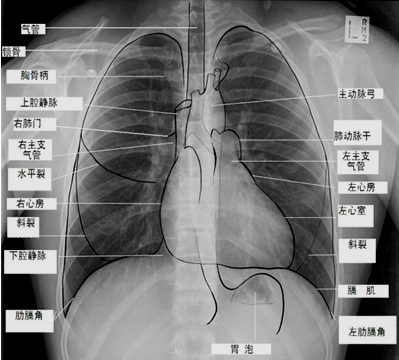

正常胸片